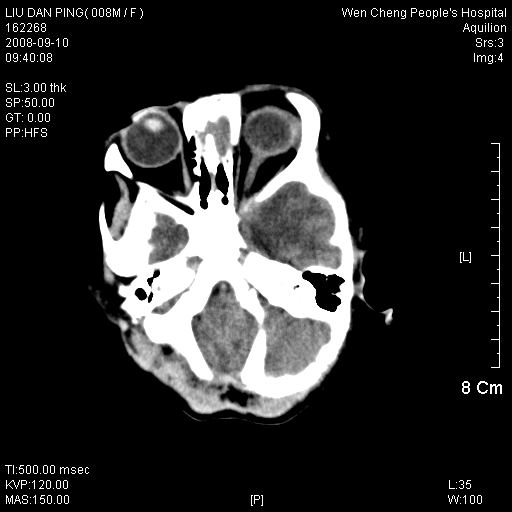

以下是引用卜一在2008-9-10 16:21:00的发言:[br]髓母细胞瘤伴梗阻性脑积水!支持![br]髓母细胞瘤特点:—般直径大于3.5cm,位于后颅凹中线之小脑蚓部。累及上蚓部的肿瘤延伸到小脑幕切迹之上,ct平扫肿瘤多呈均匀一致的高或等密度病灶,增强检查呈均匀一致的强化。病灶中有小坏死时,平扫亦可呈不均匀之混杂密度,注药后有增强。[br]

以下是引用zjzjr在2008-9-10 15:09:00的发言:[br]髓母细胞瘤伴梗阻性脑积水.